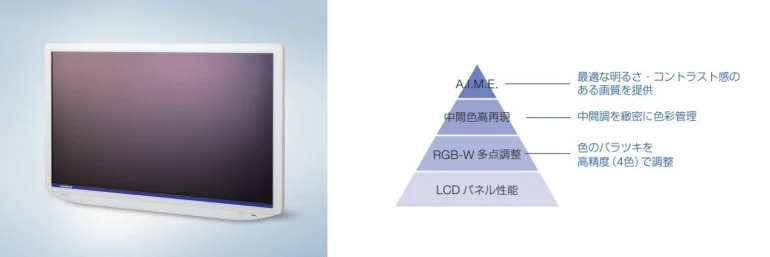

4K対応、新A.I.M.Eを搭載した高解像度の内視鏡用モニター「OEV321UH」

当院では、内視鏡画像を映し出すモニターにもこだわっております。高性能カメラと最上位機種の内視鏡システムであっても、検査医が実際に病変を確認するモニターが鮮明でなければ意味がありません。当院では、オリンパス社製最大の32インチ4K画像モニター「OEV321UH」を導入しております。特徴として、高輝度から低輝度までRGB-Wと中間色の色を調整・管理することで、優れた色再現性を実現します。さらにA.I.M.E.(Advanced Image Multiple Enhancer)機能によって、ノイズを増やすことなくシャープで鮮やかな画像が再現、質感の再現性も向上させ、より精細な観察が実現されます。